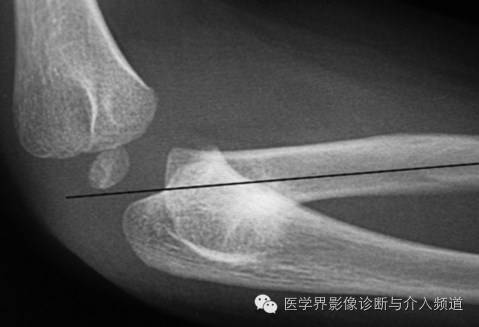

17、Nuresmaid’s Elbow

桡骨小头脱位。受伤机制为过度牵拉前臂,如家长拉着小孩上台阶。X线表现为桡骨骨干中轴线不经过肱骨小头骨骺中心。